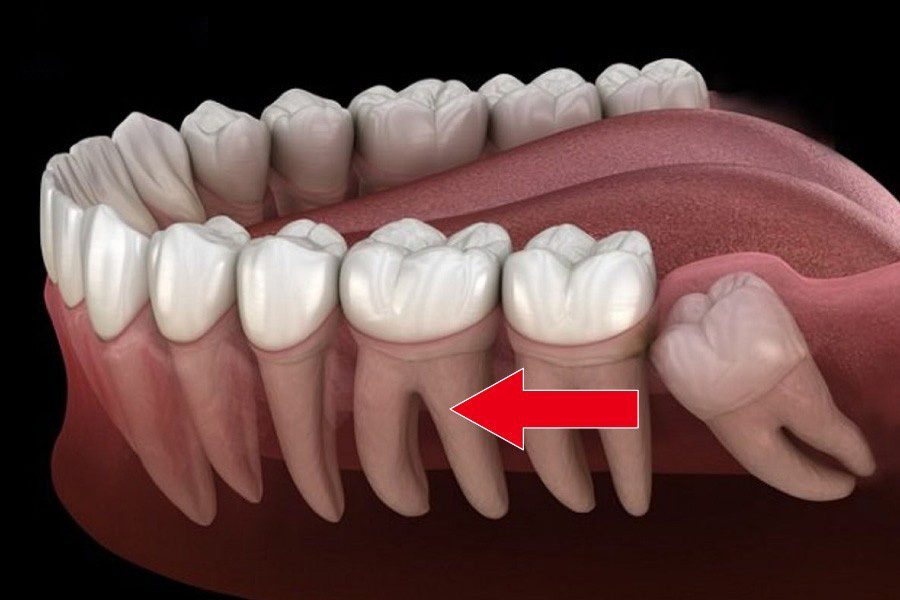

- Góc mọc của răng khôn: Góc mọc của răng khôn cũng có thể ảnh hưởng đến kết quả cuối cùng. Nếu răng khôn mọc sai hướng, nó có thể tác động lên các răng lân cận và gây lệch hàm.

Răng khôn mọc sai hướng có thể tác động đến các răng kế cận và làm lệch hàm